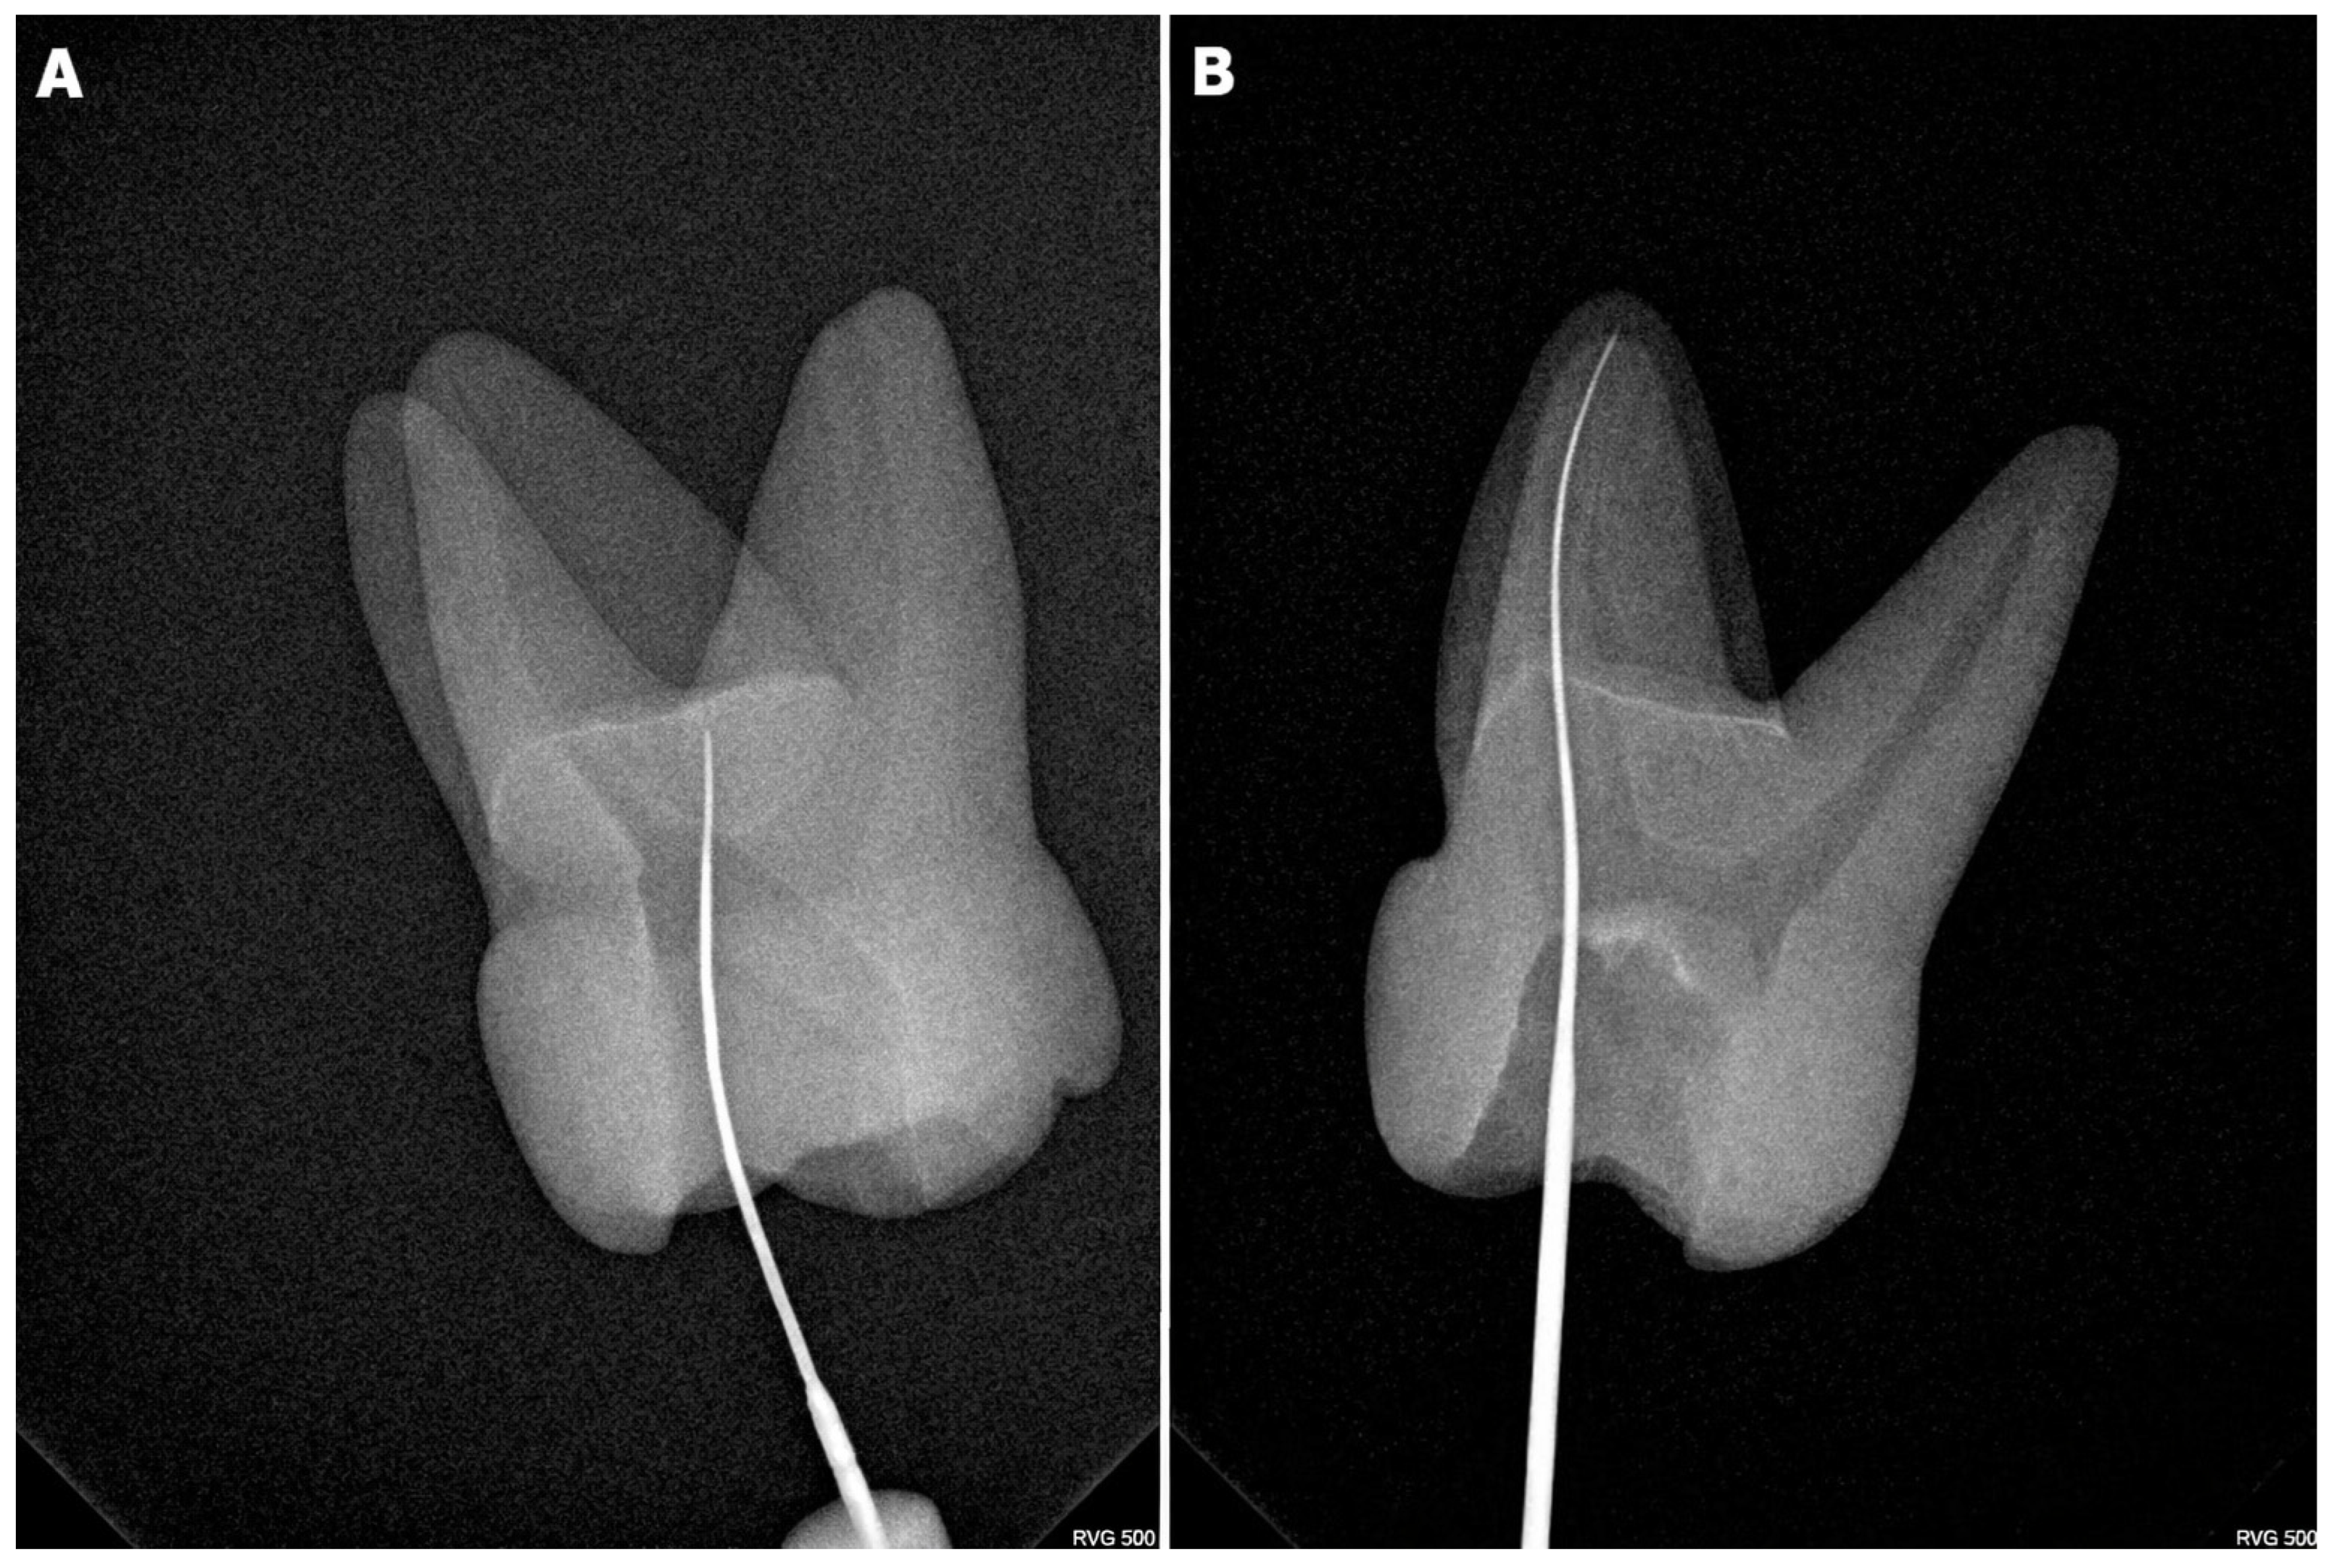

2.1. 3D-Printed Tooth Model

2.4. Clinical Procedures

2.4.2. Step 2: MB2 Canal Detection